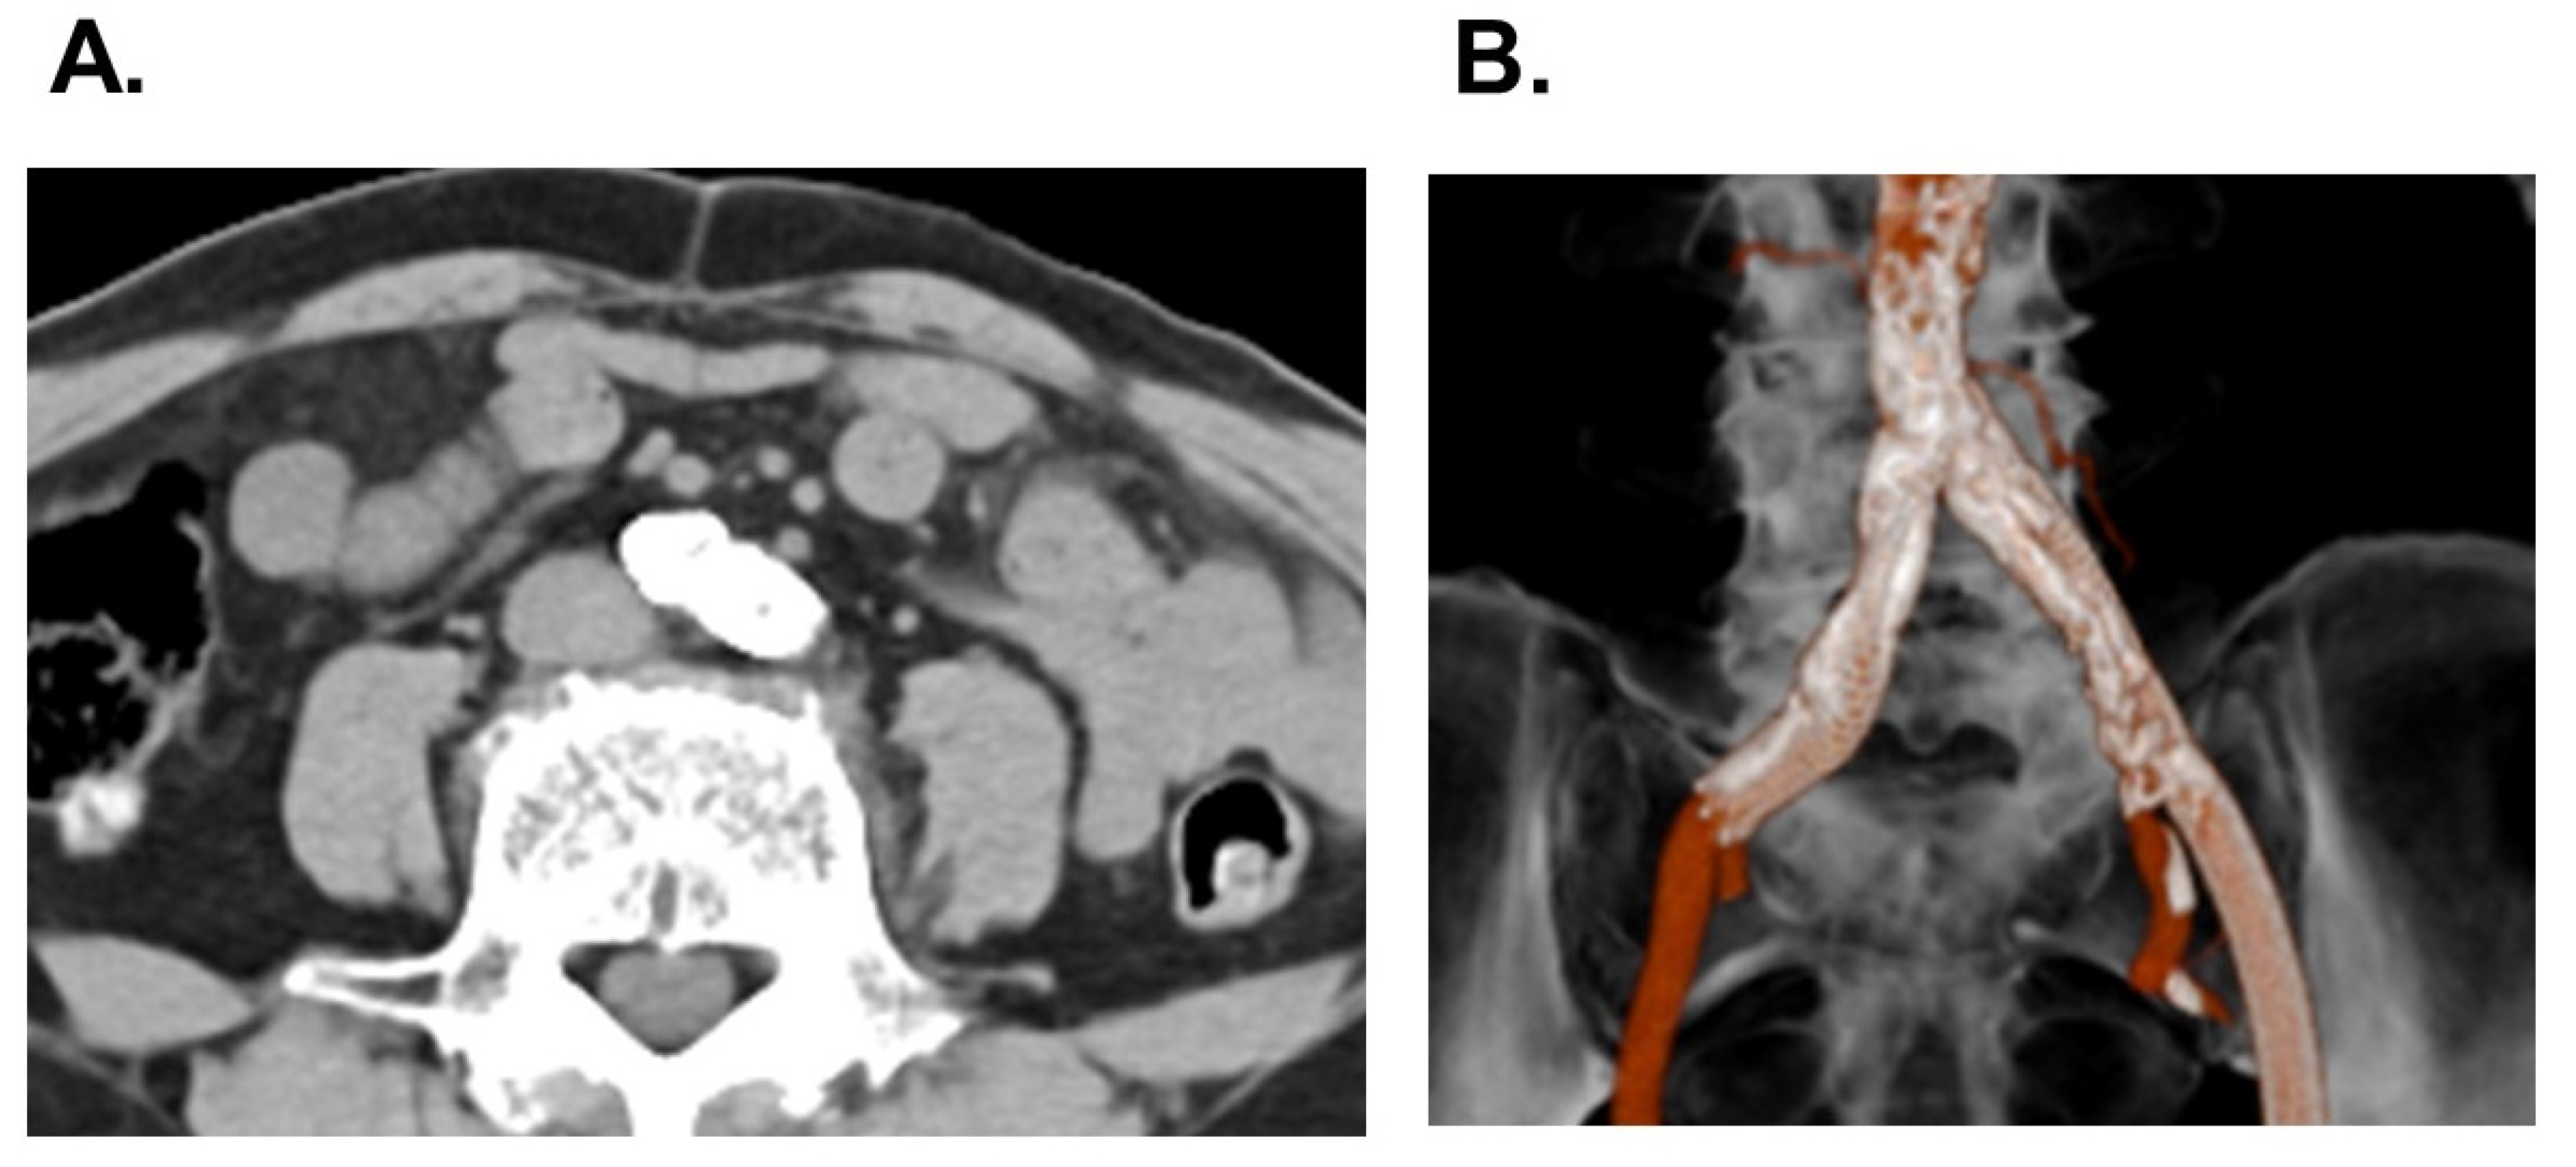

Abdominal computed tomography showed stents in the bilateral common iliac arteries. However, in-stent lumens were very small: 1.2 mm in the right artery and 2.5 mm in the left artery (Figure 3A,B). The EURO II score was 6.1% and the STS score was 8.0%. The heart-valve team discussed therapeutic strategy and decided to perform a percutaneous coronary intervention and TAVR.

Figure 3. Abdominal computed tomography as a horizontal view (A) and three-dimensional view (B) on admission, possessing bilateral common iliac stents with small in-stent lumens.